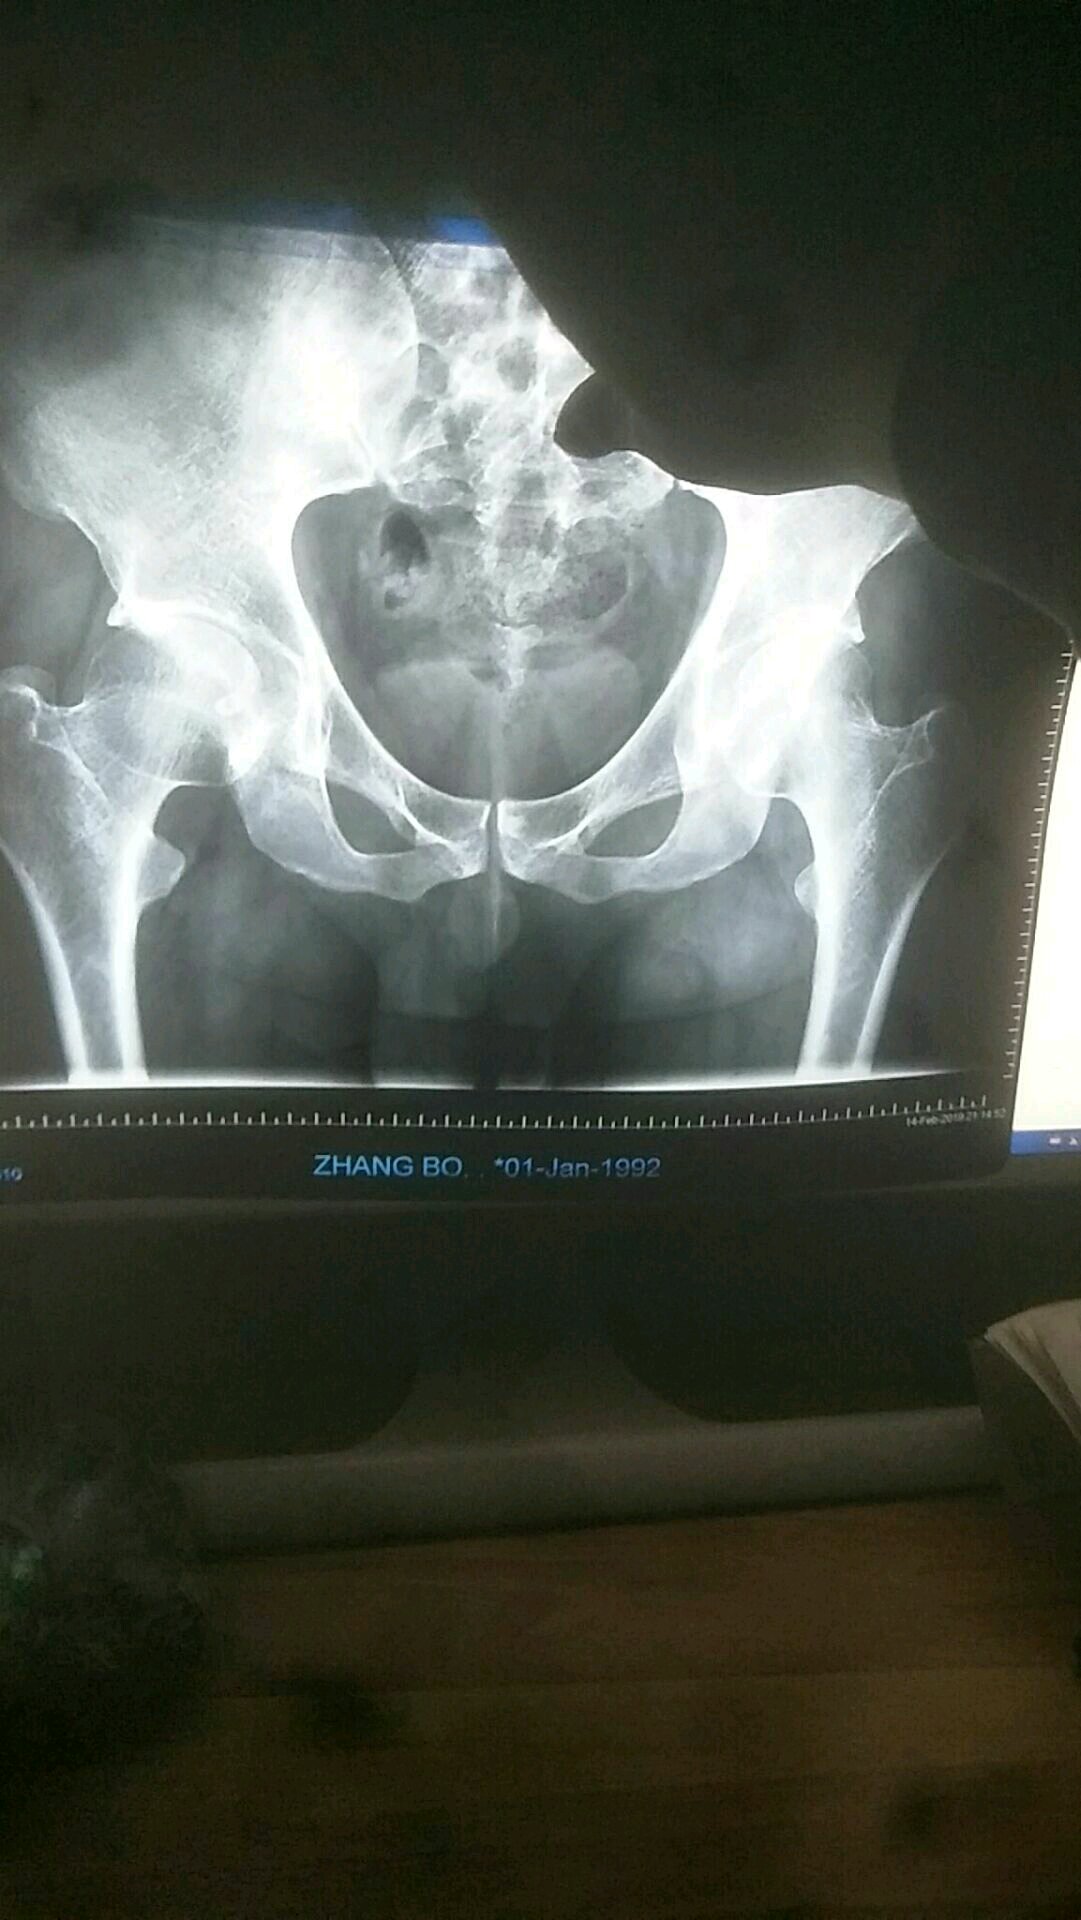

没看出骨折,是位移了吧

有点骨裂,保守治疗

医生说没看出来骨折

拍了核磁了,没有骨折